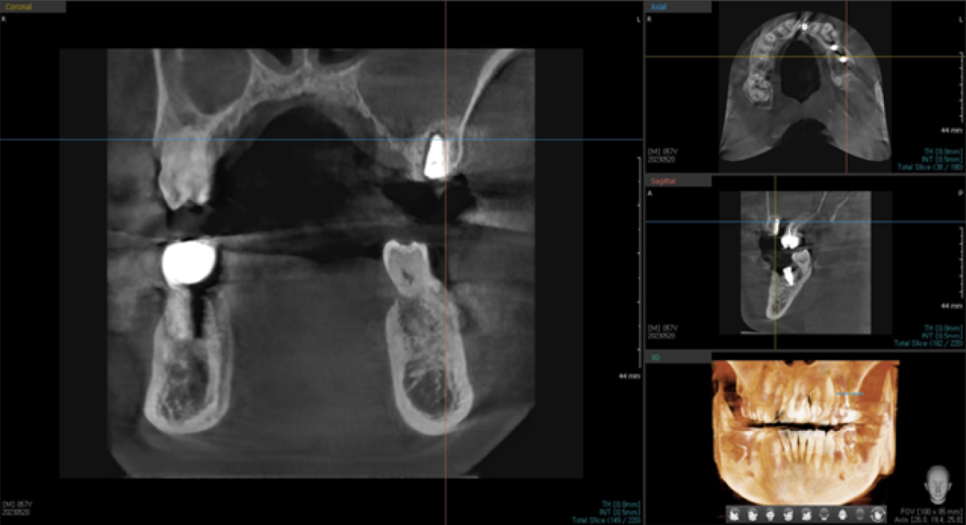

위에서 잠깐 말씀드린 것처럼,

임플란트를 식립할 뼈의 두께가 얇기 때문에

상악동 거상술을 시행해야 하는데,

3차원 CT상으로 상악동에 염증이 보였습니다.

염증치료를 위해 이비인후과 치료를 병행하였습니다.

이비인후과 치료를 병행 후에,

다시 3차원 CT를 촬영하여 상악동 내에 염증이 줄어든 것을 확인하고

왼쪽 위 임플란트 식립 수술과 상악동거상술을 진행하였습니다.

상악동 거상술도 잘 되고,

뼈이식도 하얗게 잘 된 것을 보실 수 있습니다.